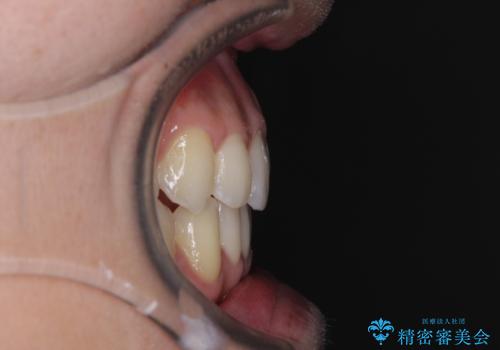

ディープバイトと叢生 インビザラインによる矯正治療

- 前歯のディープバイトと叢生を気にして来院された患者様です。

目立ちにくい装置を希望されていたため、ワイヤー装置とインビザラインを提案したところ、インビザラインを希望されました。

上下ともに叢生が認められたため、親知らずすべてを抜歯し、歯列全体を後方へ移動させることで歯列を整えることとしました。

ディープバイトもデコボコも改善され、気になっていた銀歯もセラミックとなり、患者様には大変満足していただきました。